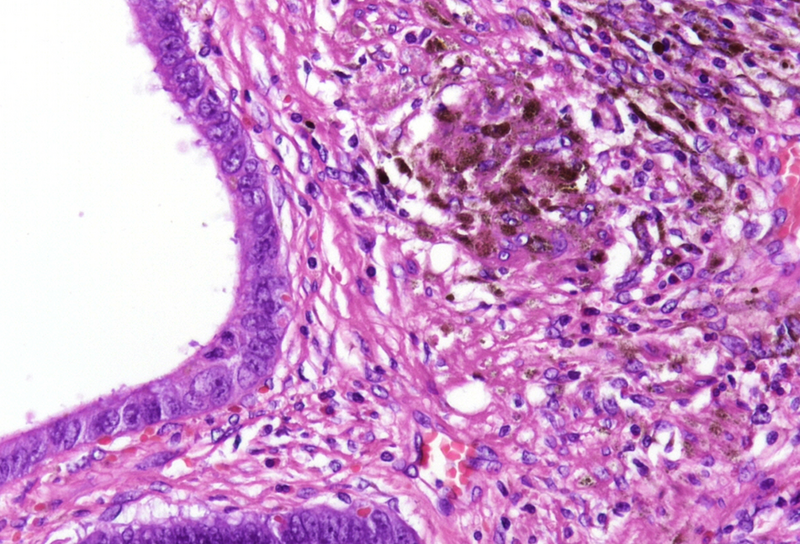

Notably, the lesion demonstrated beginning pseudo-invasion, defined by the presence of misplaced benign glandular elements extending into the upper part of the stalk. There was mild inflammation of the lamina propria, abundant hemorrhage and hemosiderin-laden macrophages were also observed (Panels E-F). Immunohistochemistry for desmin and smooth muscle actin (SMA) was performed to highlight the smooth muscle fibers (compare Panel B) and emphasize the typical lobulated and arborizing architecture of this type of polyp.

A well-recognized diagnostic pitfall in the histopathologic evaluation of PJPs is the phenomenon of pseudo-invasion, observed in approximately 10% of cases and preferably in the small bowel. This feature can closely mimic invasive adenocarcinoma. Pseudo-invasion refers to the misplacement of benign epithelial glands into the submucosa, muscularis propria, or even the serosa, often accompanied by stromal reaction and hemorrhage. This phenomenon is most commonly seen in pedunculated polyps and is believed to result from mechanical forces, including peristalsis, prolapse, and traction on the polyp stalk.

Histologically, pseudo-invasion is defined by benign-appearing glandular epithelium, typically lined by mucosa identical to the surface component, without significant cytologic atypia. These glands are usually accompanied by lamina propria-like stroma, rather than a desmoplastic reaction, and there is typically no evidence of destructive stromal invasion - features that help differentiate it from true carcinoma. The presence of mucus lakes is also characteristic.